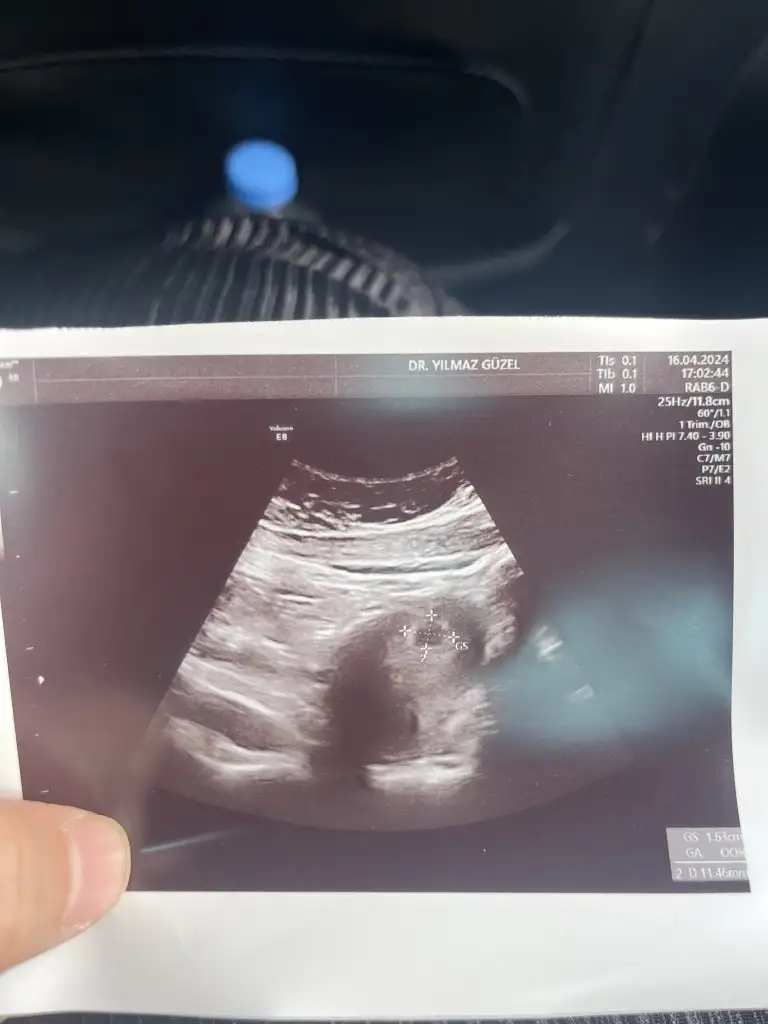

Merhaba.5+2 . Kese var ama bebek gözükmedi. Benim ultrasoni da bakabilir misiniz rica etsem😢

Merhaba bebegi gorup kalp atisini diymaniza cok sevindim. Adetiniz kac gun gectikten sonra gordunuz bebeginizi. Benim adet gunumun gecmesinin 13.gunu 6 haftalik gorunuyor kesem 12mm olmus yolk var ama icinde bebek yok.. yardim eder misiniz sizinde oyle miydi? Saglikla bebginizi kucaginiza almanizi diliyorum. 💜

Bende ayni durumdayim 6 haftalik kese 12mm yolkta var ama bebek yok :KK43: insallah 10 gune olusur.mucizem benle kalir:KK43: seninde oyle insallah💜💜